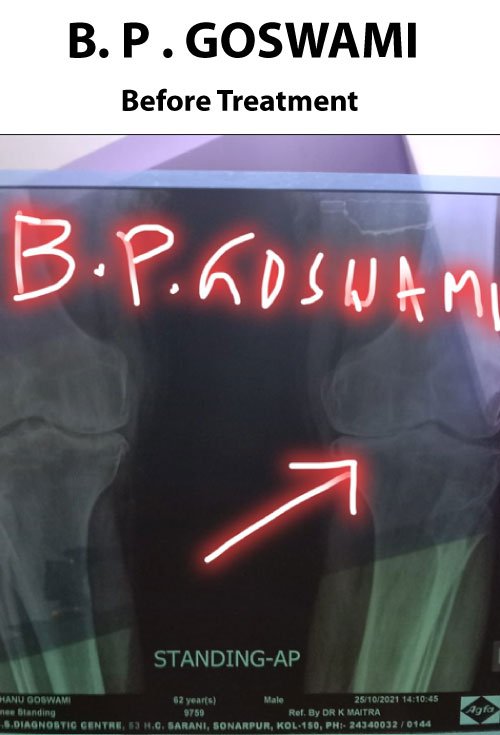

B. Goswami

I suffered from massive knee pain and difficulty walking. I had almost decided on knee replacement surgery, but after visiting Dr. N. Aman and taking 30 sittings of his special treatment, I realized surgery was not needed! Even after 6 months, I can still walk normally without problems.